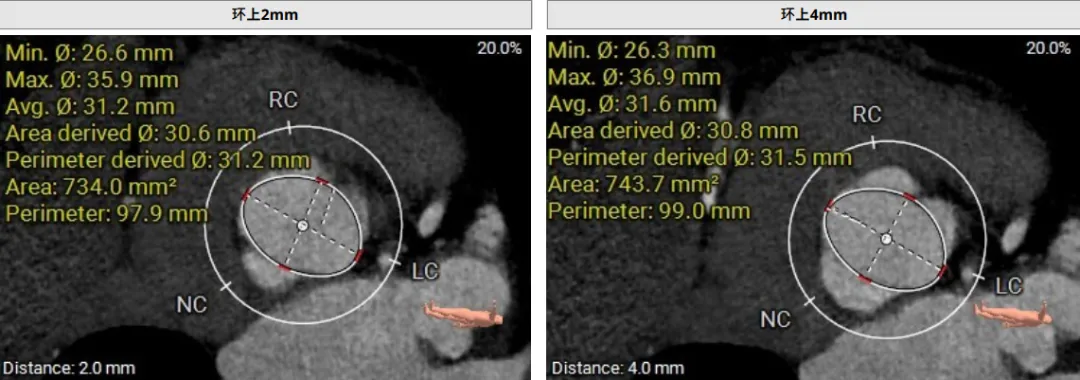

该患者术前CT评估提示:主动脉瓣Type-I型,瓣叶稍增厚,左右冠窦瓣叶交界粘连,无冠窦瓣叶轻微钙化,存在三个瓣窦,分布不均匀,左右冠窦融合;主动脉瓣环周长折算直径32.6mm;左心室流出道周长折算直径32.0mm,无钙化,无狭窄;STJ直径36.2mm,升主动脉直径38.6mm;左侧冠脉10.4mm ,瓣叶长10.8mm;右侧冠脉18.7mm,瓣叶长11.2mm;双侧冠脉开口高度可,无钙化;心尖-主动脉夹角偏大,左室主动脉夹角为120°;